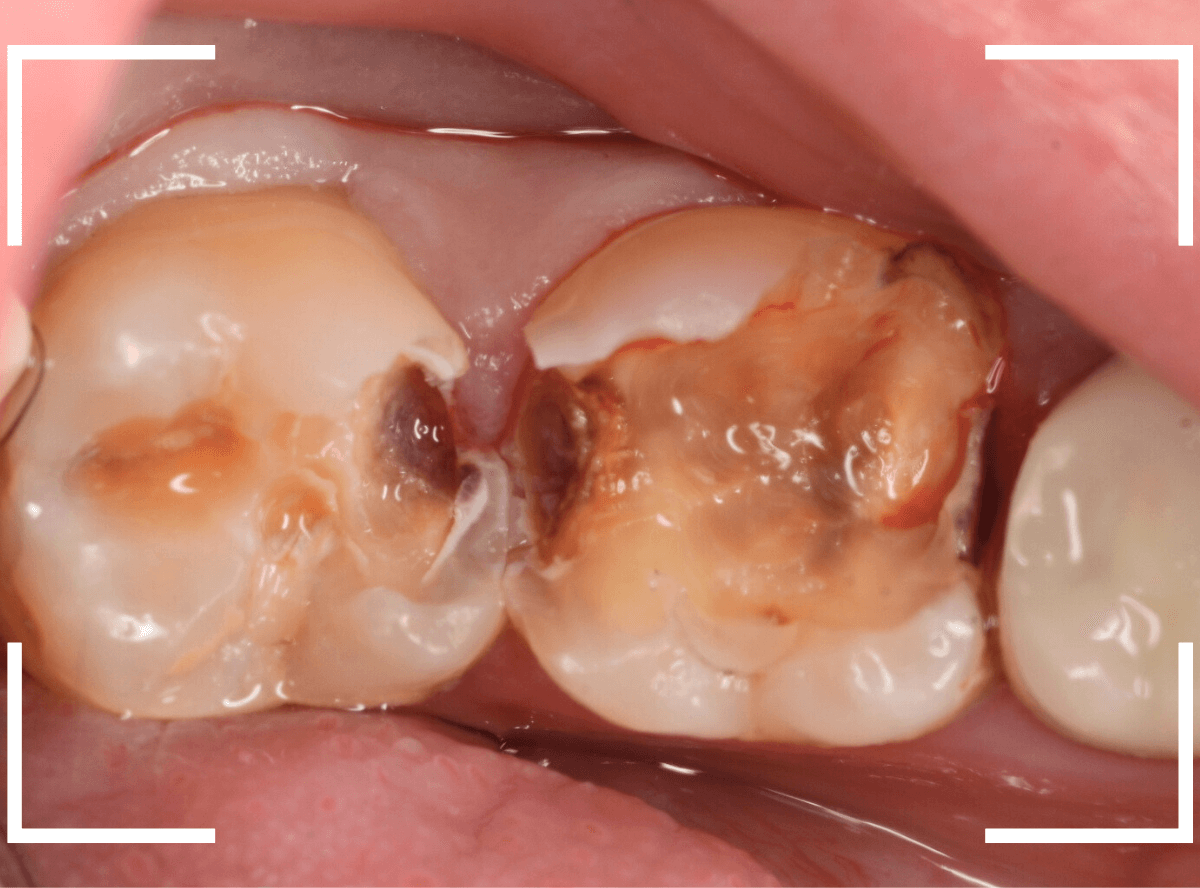

金属を外して、ある程度虫歯を除去したところです。

金属の下にしいてあるセメントも劣化してますので、中が虫歯になっていないかどうか、セメントも除去して調べます。

エナメル質付近はタービン、深めの虫歯の部分はコントラを使って、丁寧に虫歯を除去します。

8~9割ほどの虫歯が除去できたかというところですが、

赤く染色されている部分などがまだ虫歯が残っている部分です。